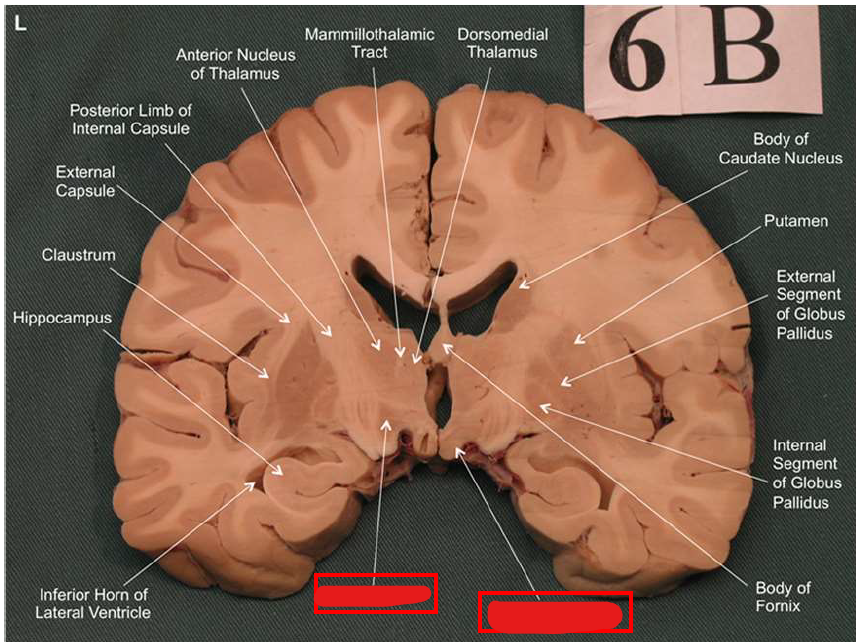

What is the fornix of the hippocampus?

Hippocampus output pathway (C-shaped)

Connects hippocampus to hypothalamus/mamillary bodies

Carries information to and from hippocampus

Important for memory consolidation and retrieval

What is this?

hippocampal fornix